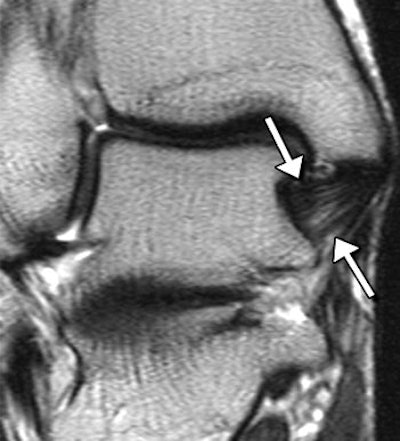

| Posterior TTL (posterior portion of the deep layer of the MCL complex) in asymptomatic 28-year-old woman. Above, corresponding drawing. Middle, T1-weighted coronal MR image (572/14). Below, T2-weighted coronal MR image (4130/86). The posterior TTL (arrows) originates from the upper segment of the posterior surface of the anterior colliculus, the intercollicular groove, and the anterior surface of the posterior colliculus. The fibers insert onto the medial surface of the talus. A typical striated appearance is seen on both T1- and T2-weighted images. |